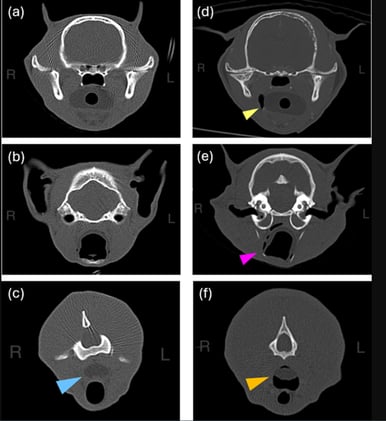

Vet Radiol Ultrasound. 2025